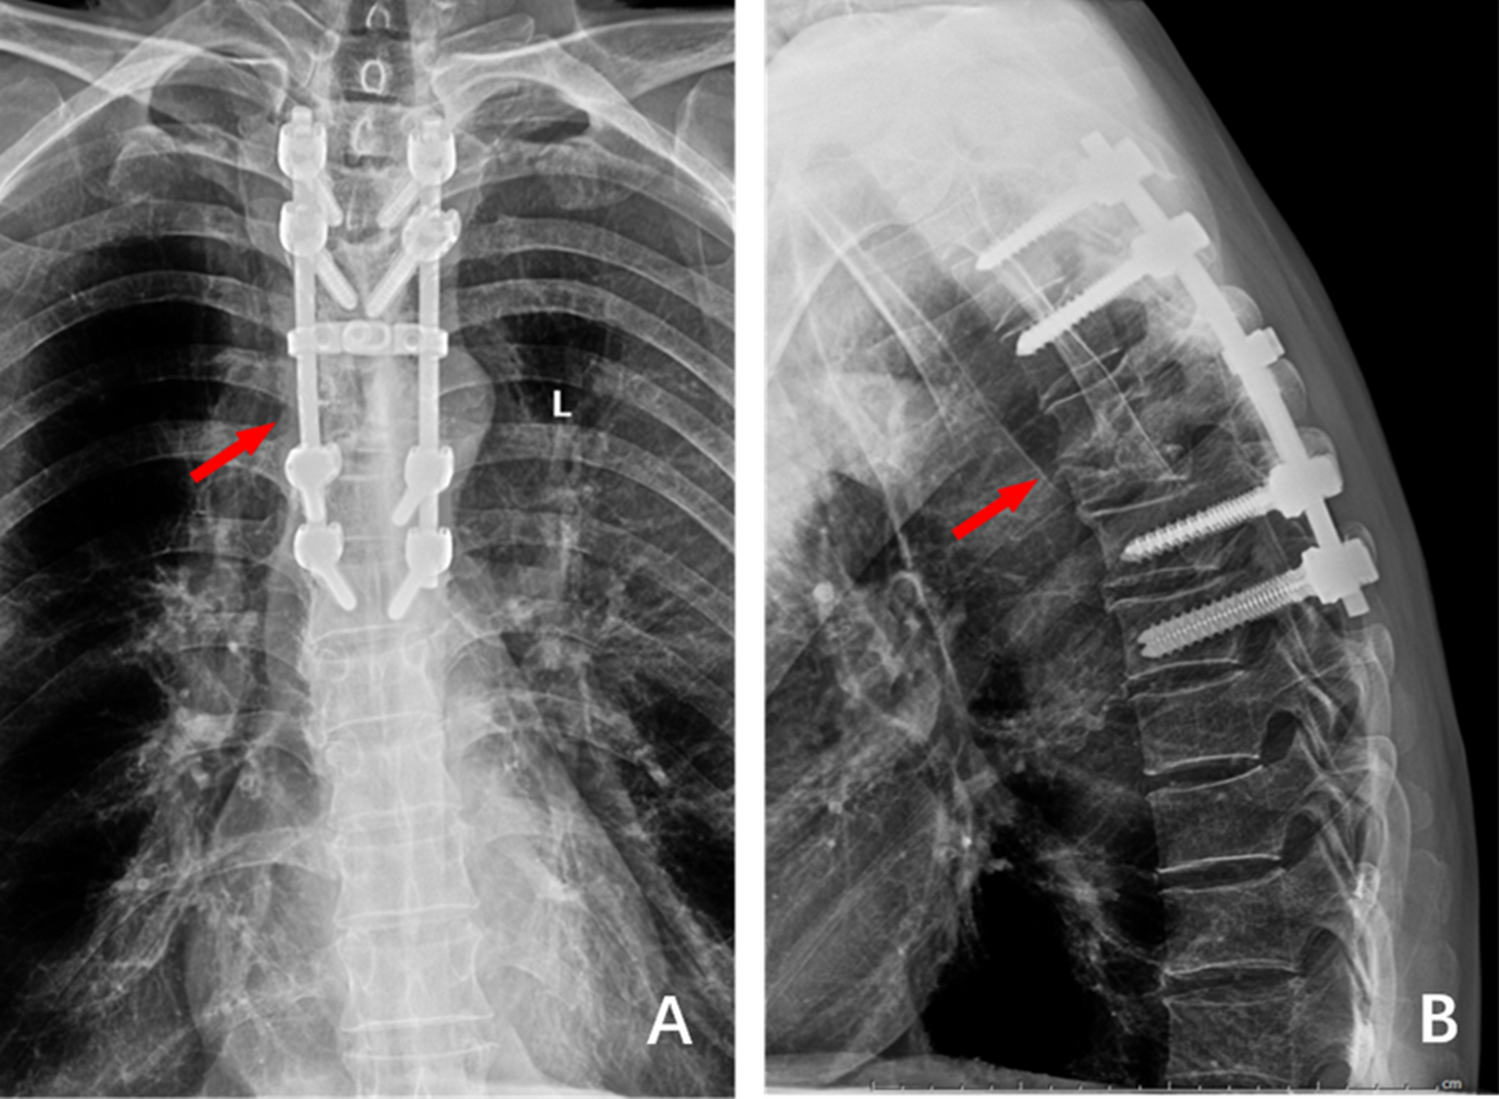

Figure 2

(A) and (B) 1 week after the operation, the frontal and lateral X-ray films showed that the internal fixation position was good, the deformity was corrected well, and The Cobb Angle was 19°.